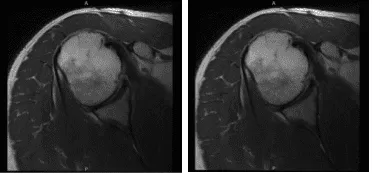

Vino a nuestra consulta con dolor recurrente en el hombro derecho que no ha mejorado. El paciente tenía debilidad en los músculos del manguito rotador. El paciente presentó un resultado de resonancia magnética que mostró que era normal, pero había una alta sospecha de desgarro del manguito rotador.

MRI-3T Hombro derecho sin contraste

Se presentó un resultado de resonancia magnética que mostró tenodesis del bíceps y posible desgarro en el manguito rotador. Evidencia de reparación previa del manguito rotador con ancla de sutura en la tuberosidad mayor. Sin embargo, los hallazgos compatibles con una rotura recurrente del supraespinoso tienen al menos una severidad moderada.

Desgarro parcial de bajo grado del tendón subescapular. Tendinosis y tenosinovitis del bíceps sin desgarros. Hallazgos que sugieren capsulitis adhesiva. Pequeño desgarro en la base del labrum anterior. Bursitis leve.